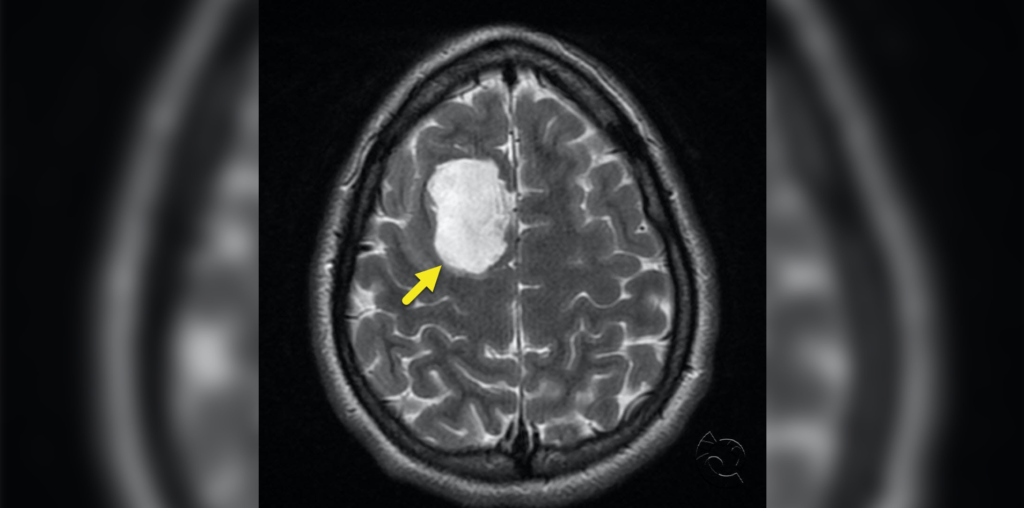

A 15-year-old undergoes brain MRI after a mild traumatic brain injury. Axial T2 (image 1), T1 postcontrast (image 2), and FLAIR (image 3) sequences show a cystic lesion involving the right superior frontal gyrus with no concerning edema or mass effect.

The lesion has mild heterogeneous signal on FLAIR and shows restricted diffusion and no contrast enhancement. These features are characteristic of an epidermoid cyst. Epidermoid cysts most commonly occur at the cerebellar pontine angle or the region of the fourth ventricle, but they can also occur supratentorially. They are usually very slow growing.

FLAIR and DWI sequences are useful for differentiation of these lesions from arachnoid cysts due to their heterogeneous FLAIR signal, higher than cerebrospinal fluid, and abnormal diffusion restriction with T2 shine-through. Surgical excision is the treatment of choice if symptomatic, but no treatment is indicated in an asymptomatic patient.